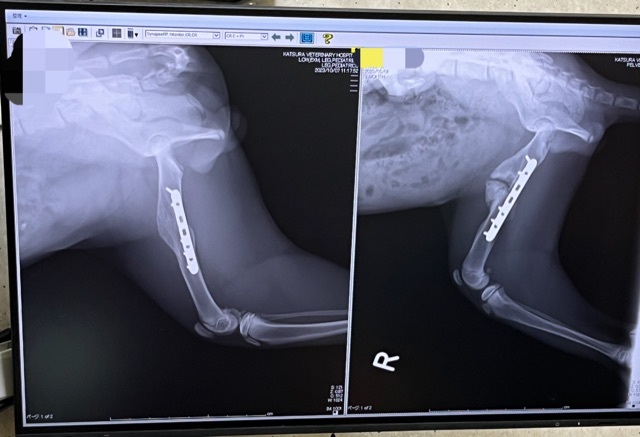

術後の検診

本日約2ヶ月ぶりの検診日でした。

骨の状態も良好でした!

レントゲン写真は左が今日撮影したものです。